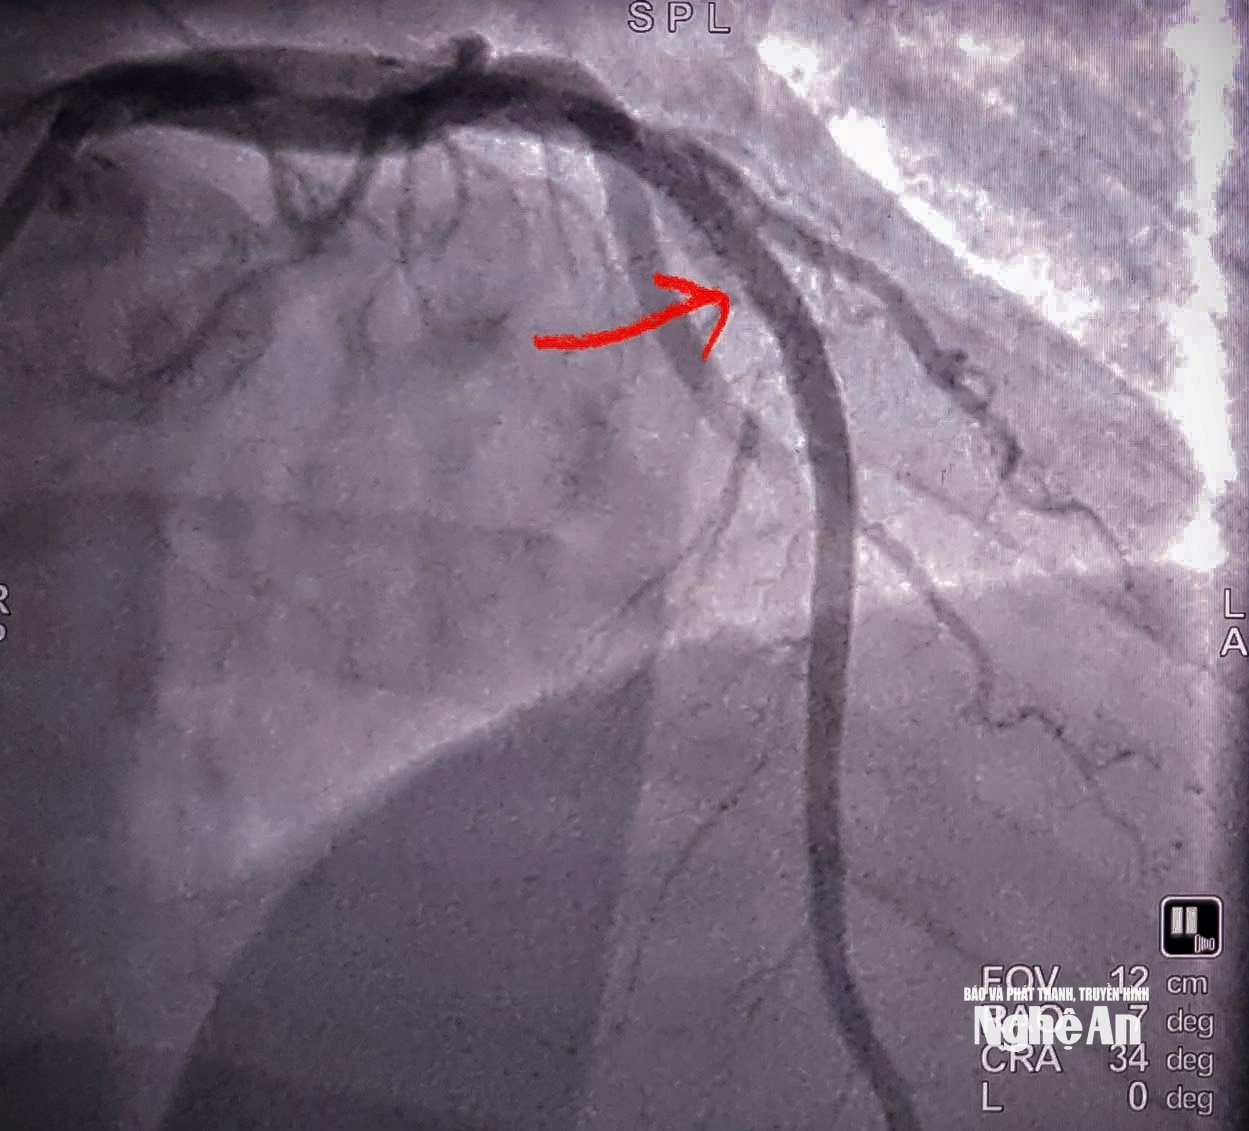

Kết quả chụp mạch cho thấy bệnh nhân tắc hoàn toàn động mạch liên thất trước đoạn II (LAD II) - nhánh mạch vành quan trọng cung cấp máu cho phần lớn cơ tim thất trái. Ê-kíp can thiệp đã nhanh chóng tiến hành nong bóng và đặt một stent phủ thuốc tại vị trí tổn thương. Thủ thuật diễn ra thuận lợi, dòng máu được tái lập ngay sau can thiệp, cải thiện rõ rệt tình trạng thiếu máu cơ tim.

Hình ảnh động mạch vành đã được tái thông. Ảnh: Bệnh viện Hữu nghị Đa khoa Nghệ An